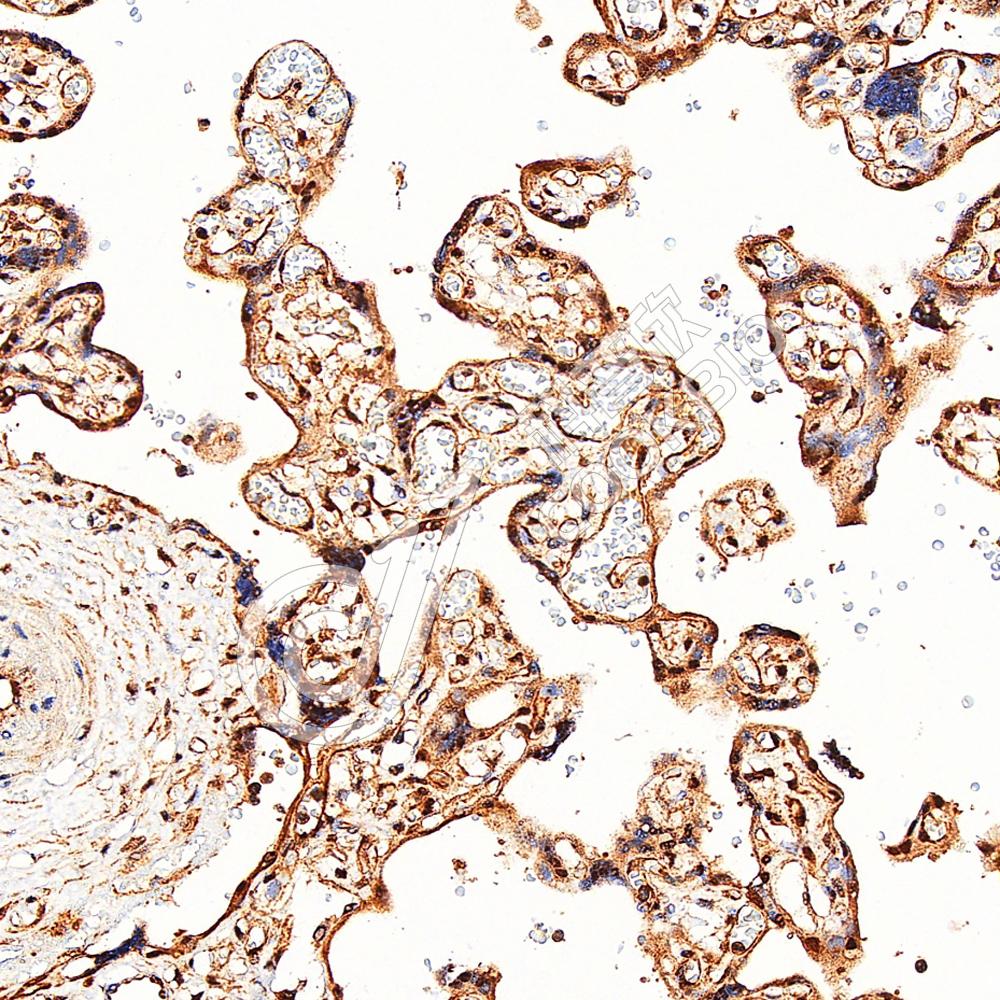

IHC检测TopBP1蛋白(货号 K1343092).

样品: 人胎盘, 4%多聚甲醛 (货号KSG1101) 固定12-24小时.

抗原修复: 柠檬酸抗原修复液(干粉, pH 6.0) (KSG1201), 98℃, 20分钟.

—抗: 1: 3000稀释, 4℃ 孵育过夜.

二抗: S-vision免疫组化多聚二抗(山羊抗兔),即用型 (货号KB3906), 室温孵育20分钟.